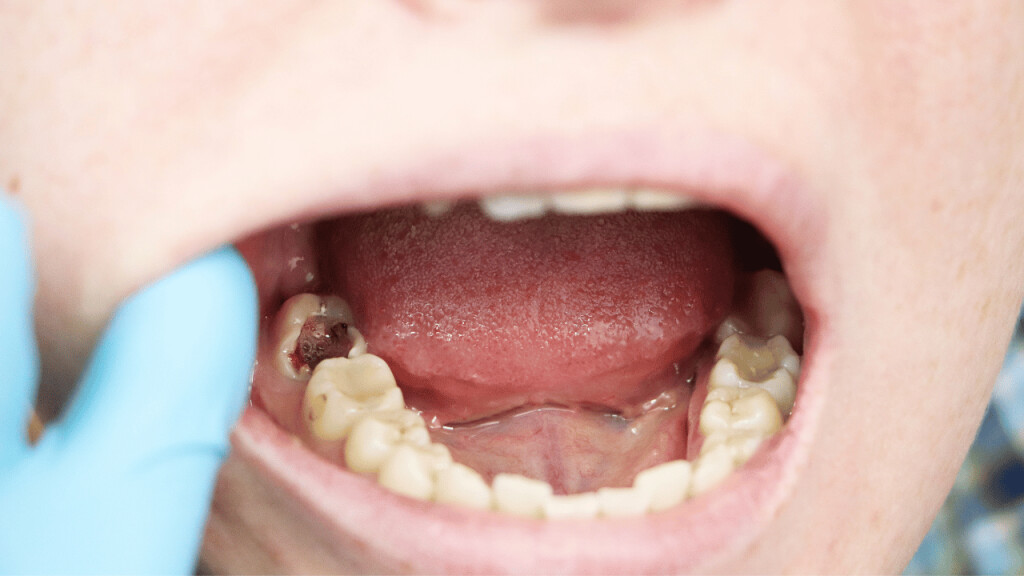

Tooth decay

As tooth decay progresses, it can reach the softer inner layers of the tooth, called dentin and pulp, resulting in sensitivity to hot, cold, or sweet foods and drinks and eventually leading to a toothache. If left untreated, tooth decay can result in an abscess, a painful infection at the root of the tooth that can cause severe pain and swelling. Adhering to your routine dental check-ups, practicing good oral hygiene, and eating a healthy diet can help prevent tooth decay and the resulting toothache.

Cavities are pretty common. As the National Institutes of Health points out, the only condition more common than a cavity is the common cold. If you've never experienced tooth decay, you might wonder, "What does a cavity feel like?" The answer depends on the stage of the cavity and what foods you eat. Some foods, such as sweets, might trigger the pain of a cavity more than others.

How Cavities Form

Your mouth is naturally full of germs. Some of those germs are perfectly healthy, but others can be harmful. When you eat something sugary, such as candy or even potato chips, or drink a sugary beverage, the germs feed on the sugars in the substance. This produces acid, which is strong enough to wear away tooth enamel if not cleaned off quickly enough. In the end, a dental cavity begins to form.

In the early stages, a cavity can be reversed, as the National Institute of Dental and Craniofacial Research notes. Brushing your teeth with a toothpaste that contains fluoride can help restore the enamel and reverse the effects of cavities.

Signs of a Cavity

What does a cavity feel like? In the earliest stages, the answer might be nothing. There are no nerves in your tooth enamel, so when the decay is in that layer, you likely won't feel a thing. Once the decay has progressed enough to reach the softer tissues inside the tooth, where the dentin and nerves are, you might notice signs of a cavity. Your teeth might feel sensitive and you could feel some pain, especially after eating sweets, hot foods or cold foods. The pain can be fairly mild or sharp and intense. Some people with cavities also feel pain when biting down.

Depending on the size of the cavity, you may be able to see evidence of it in your mouth. Cavities sometimes create visible holes in the teeth. They can also create stains that are black, brown or white on the surface of the tooth.